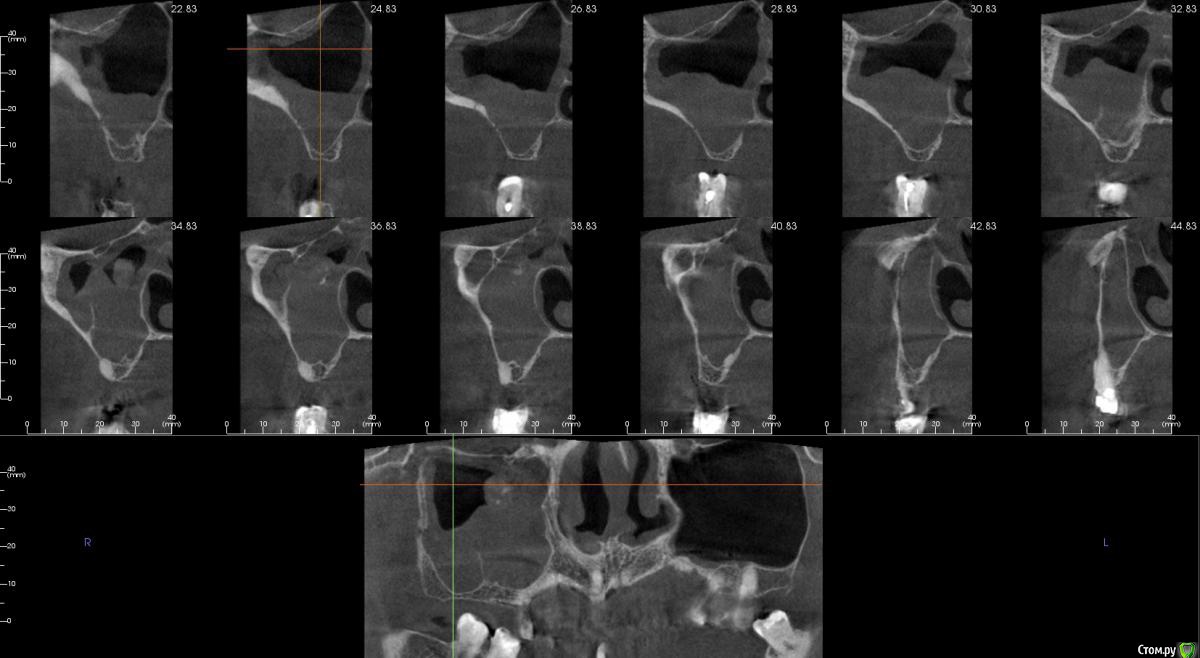

kamranchick Опубликовано 2 апреля, 2017 Поделиться Опубликовано 2 апреля, 2017 (изменено) Пациент обратился с целью восстановления жевания.удалял 16 зуб в поликлиннике, ему долбили, потом в ЧЛХ доставали что то).На кт вот такая ситуация, как посоветуете поступить? PS 1.7 и 1.8 зуб удалил. Изменено 2 апреля, 2017 пользователем kamranchick Ссылка на комментарий

колесников Опубликовано 2 апреля, 2017 Поделиться Опубликовано 2 апреля, 2017 А в чем вопрос? Пазуха чистая,можно пробовать . Ссылка на комментарий

kamranchick Опубликовано 2 апреля, 2017 Автор Поделиться Опубликовано 2 апреля, 2017 Да дыры какие то и на окклюзионной поверхности и сбоку) это и отпугнуло Ссылка на комментарий

колесников Опубликовано 2 апреля, 2017 Поделиться Опубликовано 2 апреля, 2017 Дыру закрыть можно, главное из дыры отслоится без разрывов. Рубцовска ткать прочно врастает в края дефекта,я бором прохожусь по контуру дефекта и отделяю рубцовую заплатку вместе со шнейдоровой относительно легко. Ссылка на комментарий